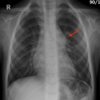

12

Q

A

Consolidación alveolar

How well did you know this?